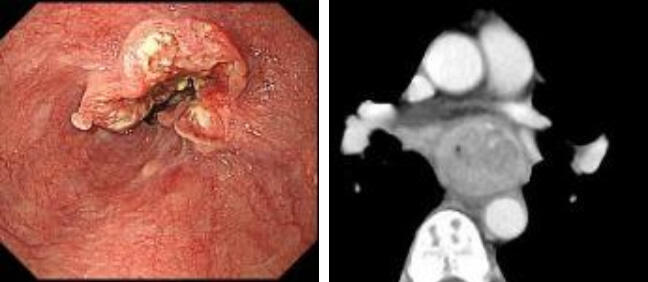

食道癌について

進行癌では食事がつかえる、体重が減る、胸の痛みや声がかすれるといった症状が現れます。早期癌では無症状で、健診の内視鏡検査などで発見されることが多いです。

食道癌の特徴

- 他の癌に比べ発育速度が早い癌です。

- 解剖学的にも治療の難しい場所に発生する。周囲に気管、大動脈、心臓、肺などの重要臓器が隣接し、増大に伴い浸潤する(癌が入り込む)おそれがあります。

- リンパ節転移を起こしやすく、粘膜下層癌(T1b)でも約40%にリンパ節転移を認めます。これは胃癌の2倍、大腸癌の4倍の頻度となります。

- 頸部付近の癌は小さいうちは注意して内視鏡観察しないと見落としやすい癌です。頸部の癌は喉頭(声帯)に近く、声を残して治療できるか、飲み込みができるかなど治療後のQOL(生活の質)に関わる問題も重要です。